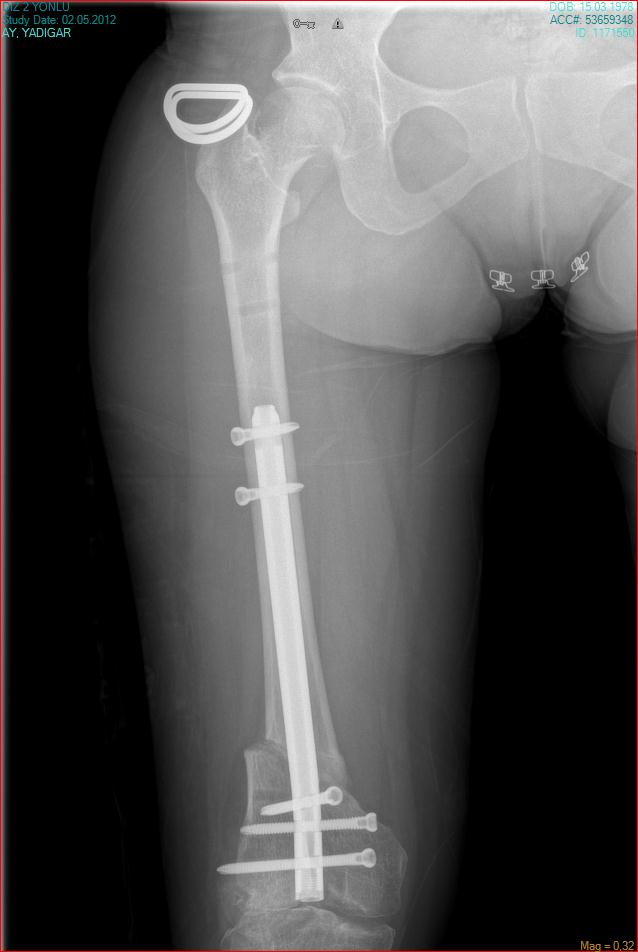

arthritis deformity surgery endoprosthesis hip prosthesis ilizarov ilizarov surgery infected nonunion knee prosthesis lengthening surgery limb lengthening surgery nonunion periprosthetic infection psodoartroz revision surgery total hip prosthesis total knee prosthesis